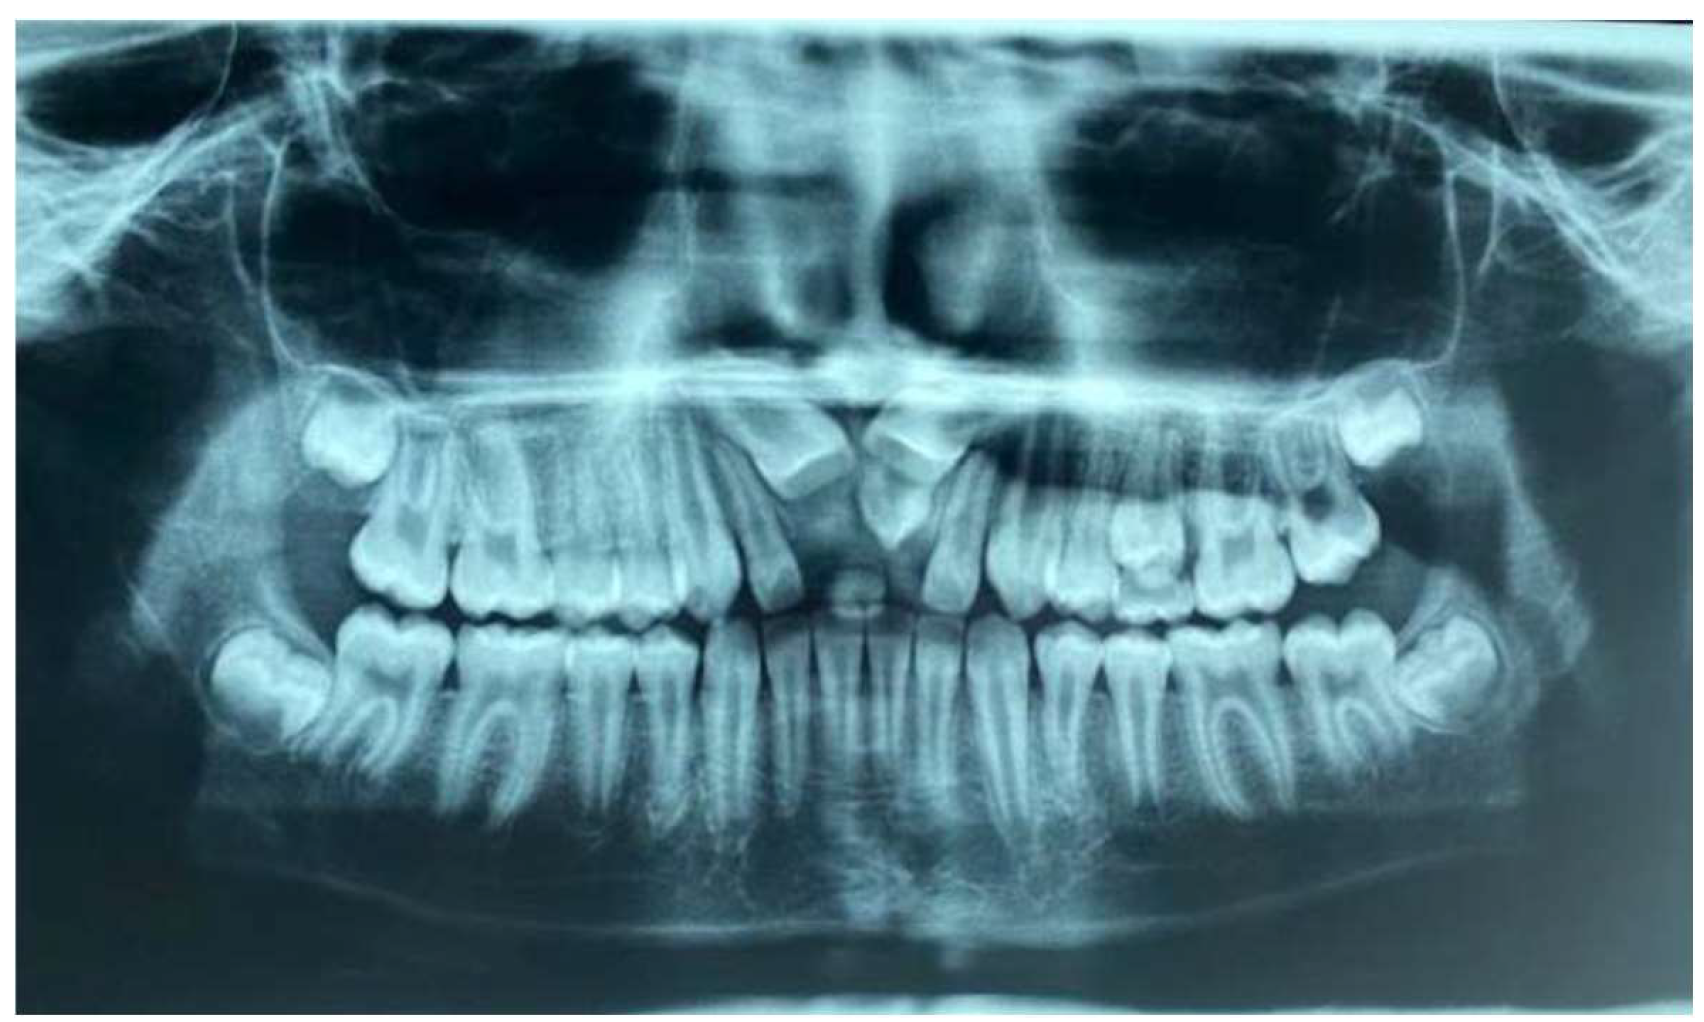

- Ortopanthomography X-ray (OPG X-ray) to evaluate the problem in relation to the entire arch, adjacent tooth and the staging of the eruption of the other dental elements.

2. Case Report

2.1. Clinical History

2.2. Clinical Exams and Diagnosis